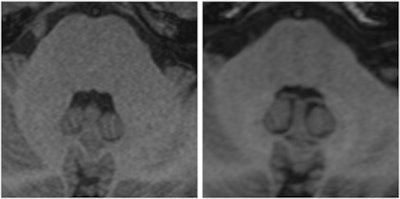

Further research has since revealed that some of the agents can undergo dechelation in patients with normal renal function, resulting in gadolinium deposits in the brain and other body tissue. The findings have shocked the imaging community -- what had been go-to contrast agents are now being viewed with some caution. With studies thin on the ground and numerous unanswered questions, radiologists have been left confused over how to approach the eight approved agents. Both the European Medicines Agency (EMA) and the U.S. Food and Drug Administration (FDA) are expected to clarify the situation and provide guidelines for use in 2017.